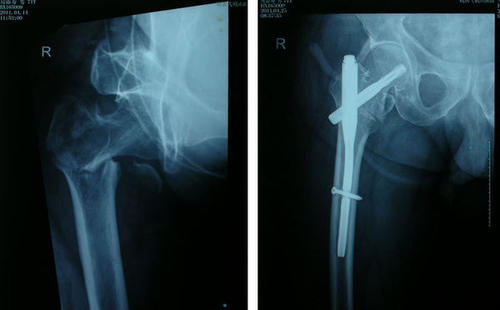

四、手术治疗还是保守治疗?

一般情况下,髋部骨折强烈建议积极进行手术治疗,这样可以尽快的缓解患者的痛苦,及早的自由活动,减少并发症的发生,研究发现,髋部骨折患者,绝大部分不是因为骨折本身去世,而是因为各种并发症。

但是手术治疗适合每一个人吗?不是的,对于一些基础疾病多,身体极度虚弱,不能耐受手术的患者只能保守治疗。